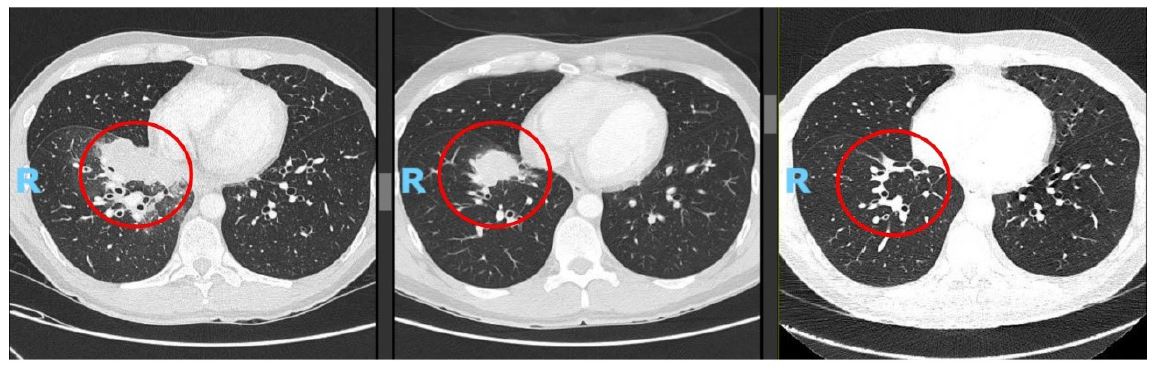

A 45-year-old male, former smoker (2 package index year) with no significant medical history, presented to Internal Medicine in May 2023 with a 4-month history of persistent dry cough and pleuritic chest pain. A chest X-ray revealed an opacity in the right lower lobe, initially of uncertain inflammatory or infectious etiology. The patient also reported a left scrotal lesion, noticed months earlier, presumed to be a lipoma and awaiting excision. A left testicular ultrasound was performed, revealing an oval-shaped lesion measuring approximately 11×5 mm (Figure 1).

Figure 1: Adjacent to the left inguinal canal, in contact with its vasculature, an oval-shaped lesion measuring approximately 11×5 mm is identified. Color Doppler reveals vascular flow; however, the lesion remains nonspecific with this modality and may correspond to a lymph node.